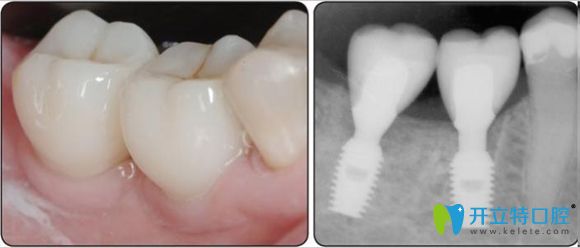

韓國(guó)登特斯種植牙示意圖